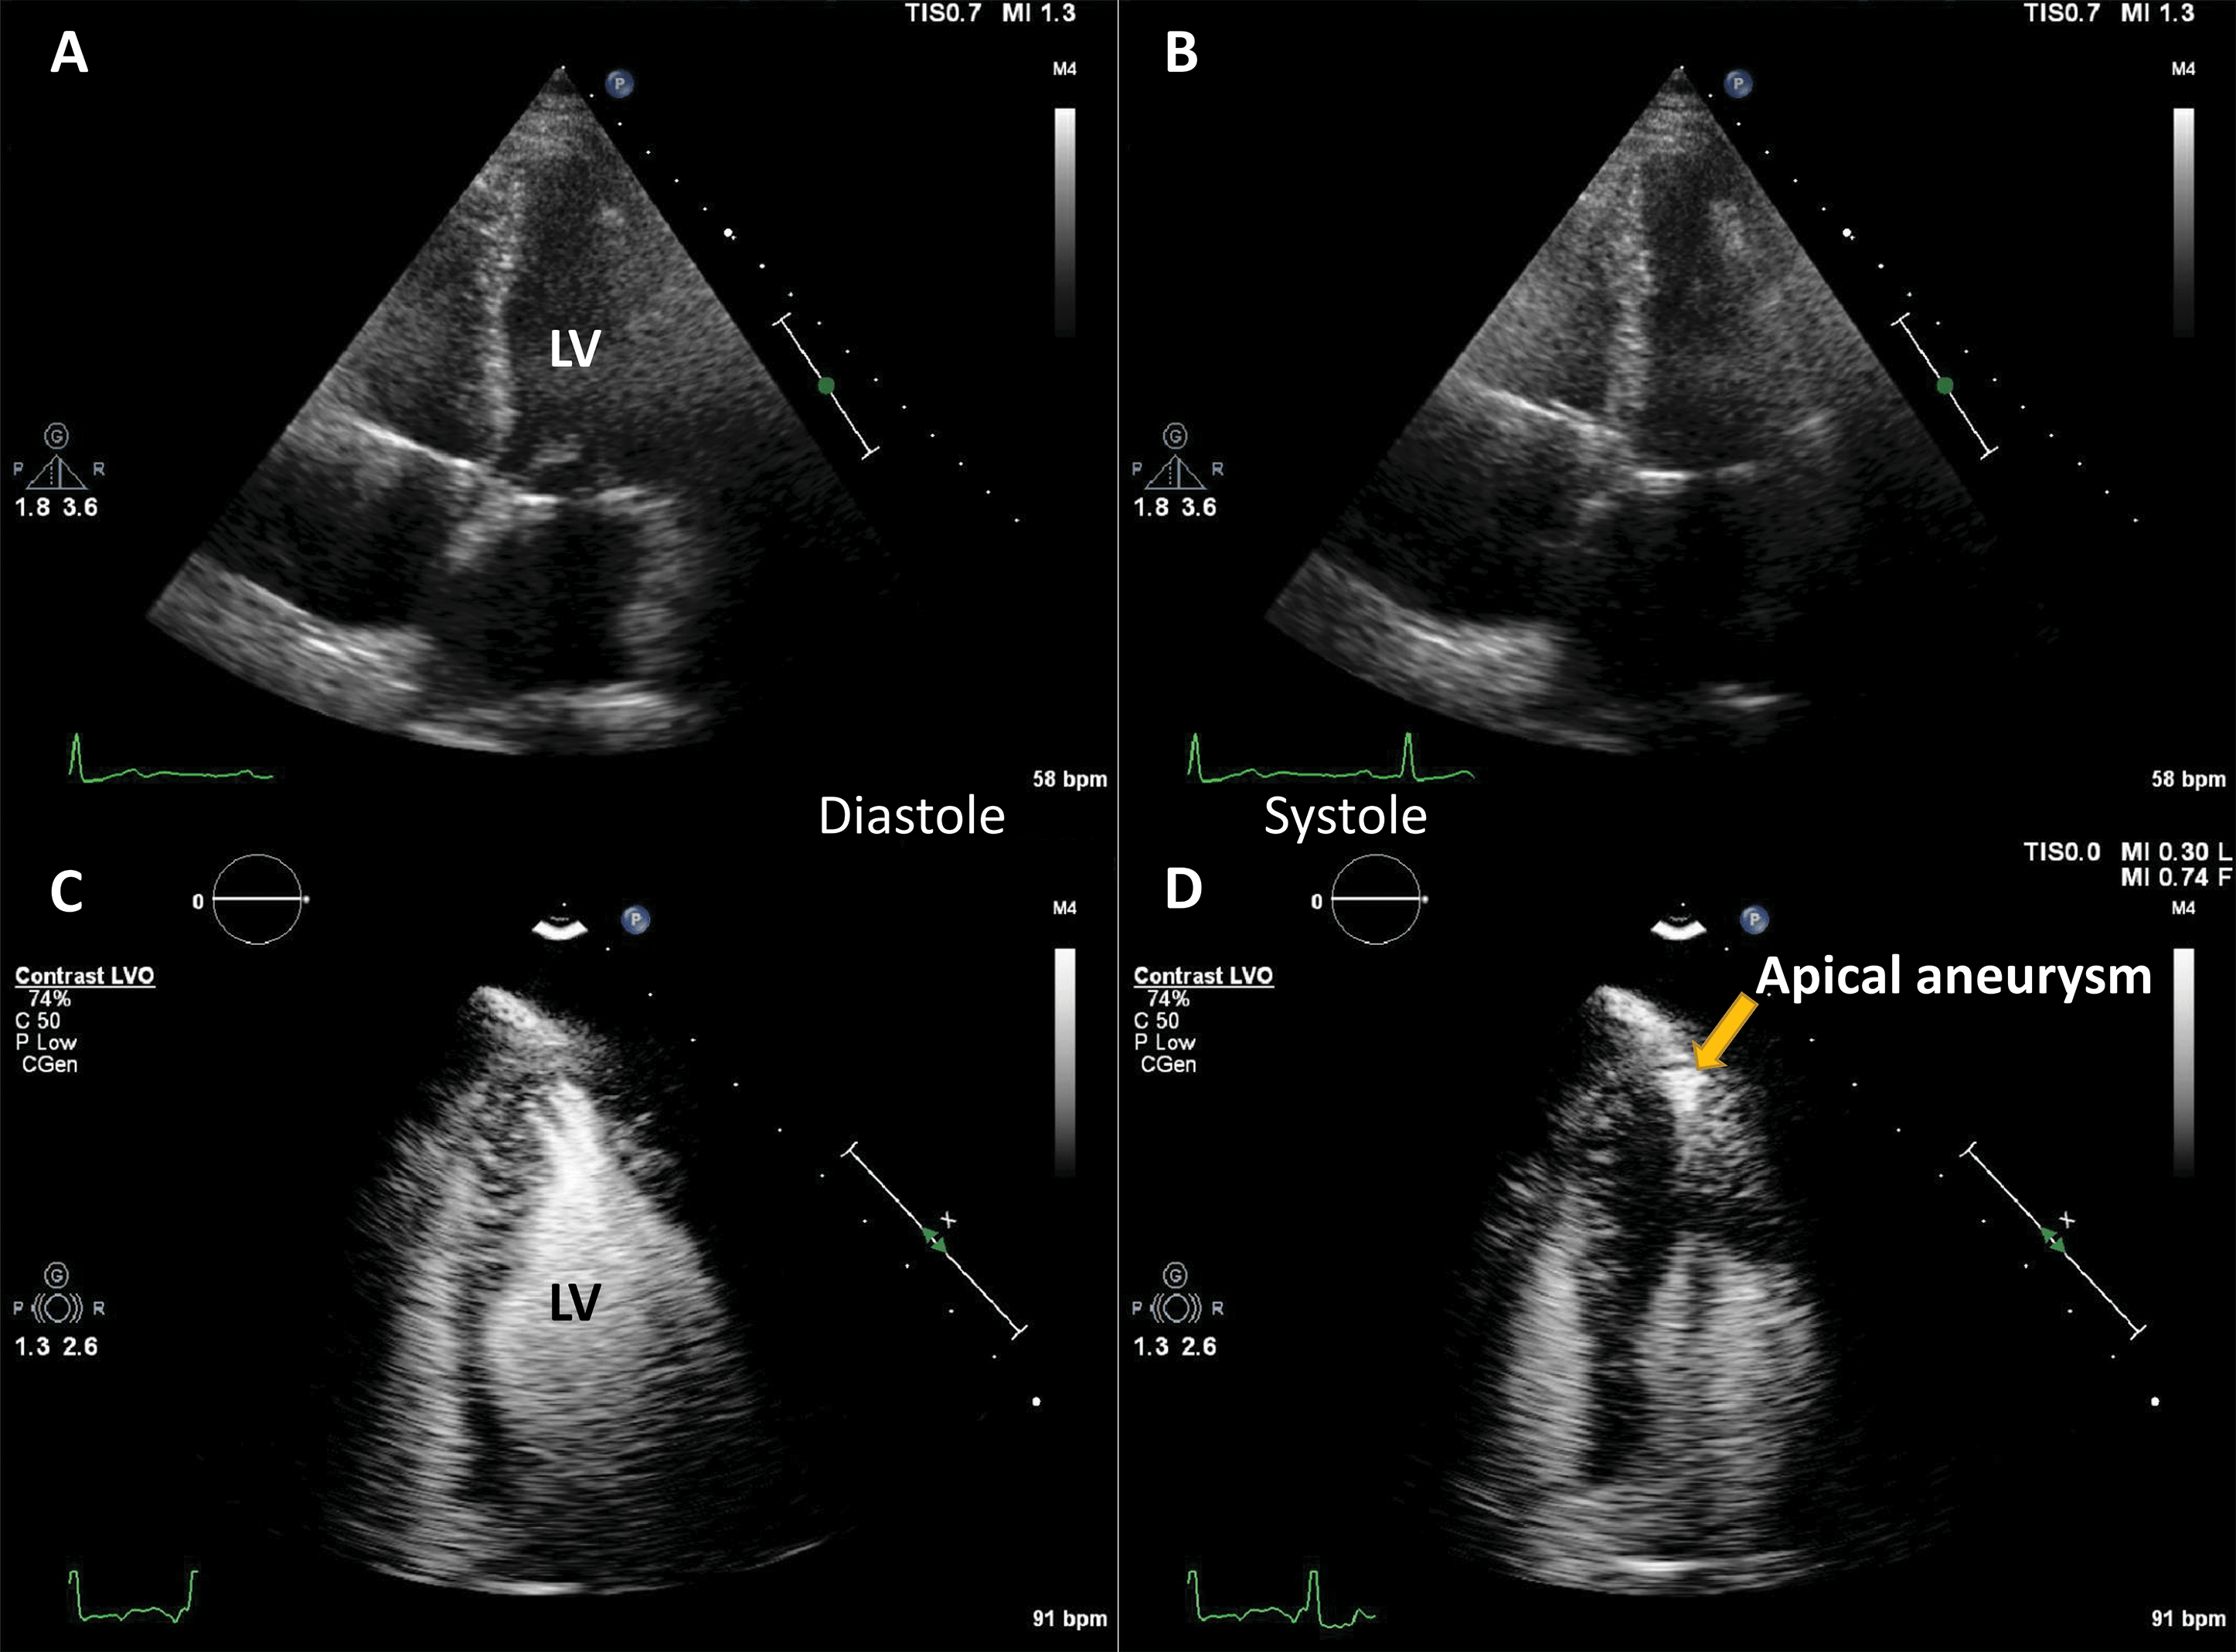

By using UEA, enhanced echocardiographic measurements of LV volumes and ejection fraction are very close to the reference cardiac magnetic resonance (CMR) values [11, 12], and significantly less variable as compared to unenhanced imaging, even if baseline images are of good quality [18]. This significant difference in quality, information and accuracy leads to a clinical impact on diagnosis and management [6, 19, 20]. Echocardiographic estimates of LV volume tend to be larger when using LVO, mainly because it aids the exclusion of trabeculae (Fig. 3), making the measurements closer to their CMR counterparts [13].

Fig. 3.Ejection fraction (EF) estimation. (A,B) Non-enhanced ultrasound images. The endocardium is not clearly visible in several segments (question marks), making the volumes difficult to assess. (C,D) Contrast-enhanced images. The endocardial border is clearly defined, allowing for a biplane volume estimation. Moreover, the LV end-diastolic volumes in contrast-enhanced images is notably larger than the one on the non-enhanced images, probably because of a combination of insufficient image quality on native images, and exclusion of trabeculae and papillary muscles on contrast images. Source: personal collection.